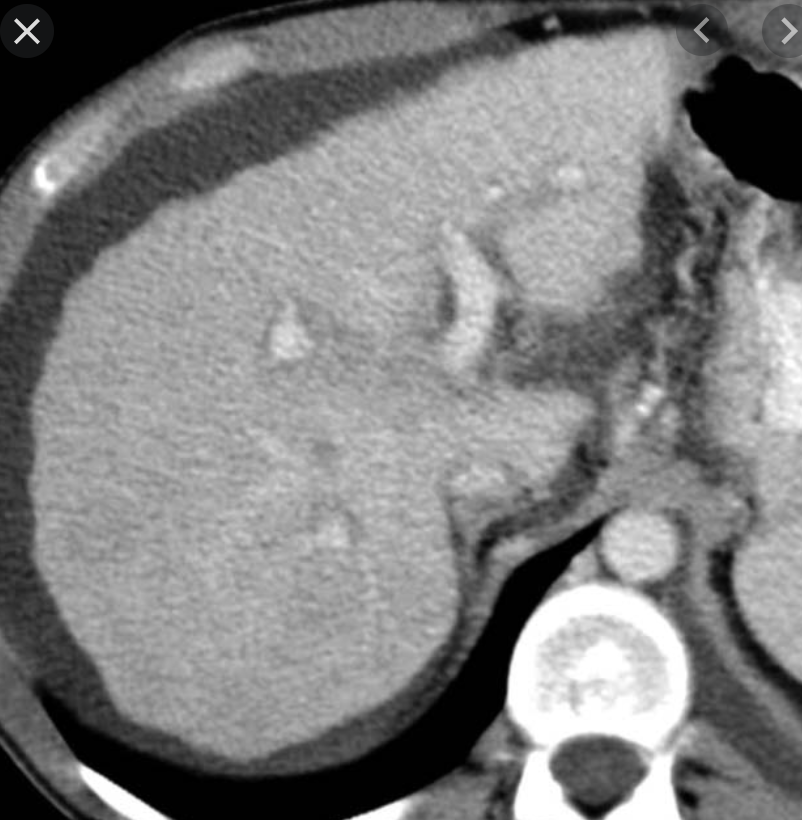

Ix: general findings; unique hepatic findings in Wilson’s.

Ix: general: hyperattenuation + cirrhosis